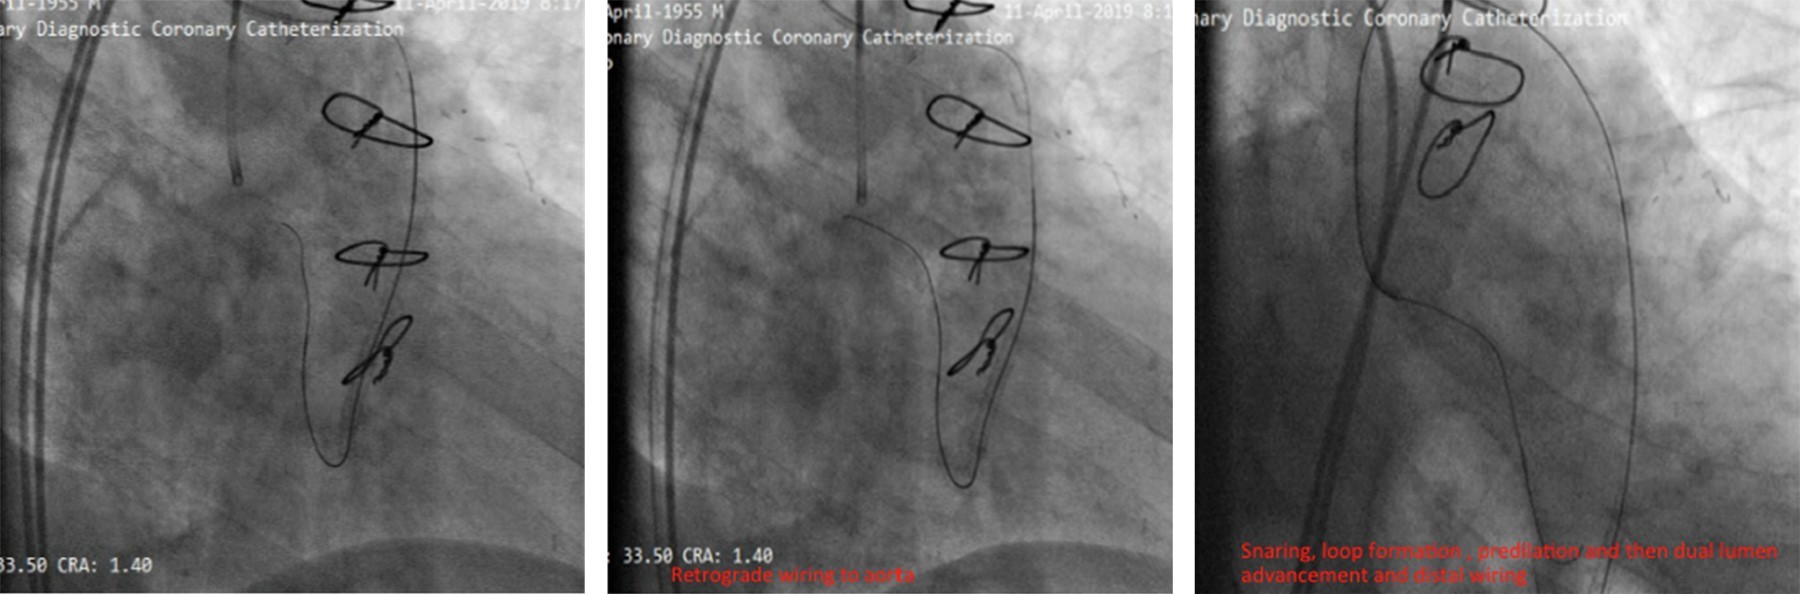

Reportamos el caso de un hombre de 78 años con antecedentes de cirugía de revascularización coronaria (CRC) e intervención coronaria percutánea (ICP) del injerto de vena safena (IVS) a la arteria marginal obtusa (MO). El paciente presentó síndrome coronario agudo y fue derivado a atención terciaria después de que la angiografía coronaria revelara reestenosis intrastent en una IVS trombótica, junto con oclusión total crónica (OTC) de la arteria circunfleja izquierda (CI). Nuestro plan inicial fue la intervención de IVS a MO debido a reestenosis del stent y trombosis. Durante el procedimiento, una rotura de balón resultó en disección y hematoma. Como intervención de rescate, se realizó stent nativo en la CI con OTC, seguido de oclusión con coil de la IVS. Surgieron complicaciones cuando el coil se desprendió y fragmentó, lo que llevó a la embolización de una partícula en la aorta descendente y la otra en la arteria femoral. Ambos fragmentos se recuperaron con éxito mediante un lazo. Este caso destaca la complejidad del manejo de las complicaciones de la ICP relacionadas con la IVS y la importancia de manipular cuidadosamente el dispositivo durante los procedimientos de colocación de la bobina.

Figura 5